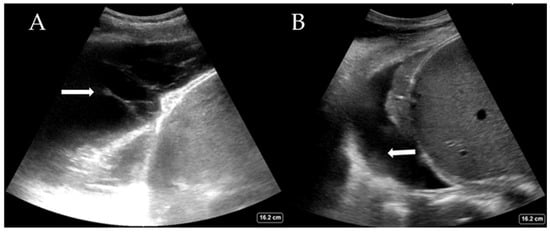

| Cardiogenic pulmonary oedema | Homogenous B-line distribution >3 per image (Figure 2A) Regular thin pleura Possible pleural effusions |

| Pleural effusion | Interpleural hypo/anechoic space (Figure 3A,B) Jelly fish sign—lung moving within effusion appears jelly fish like |

| Consolidations | Shred sign—small sub-pleural consolidations (Figure 2B) Tissue like pattern/lung hepatisation—homogeneous texture of a lobe, similar to abdominal parenchyma Air bronchograms—hyperechoic branching structure within consolidation |